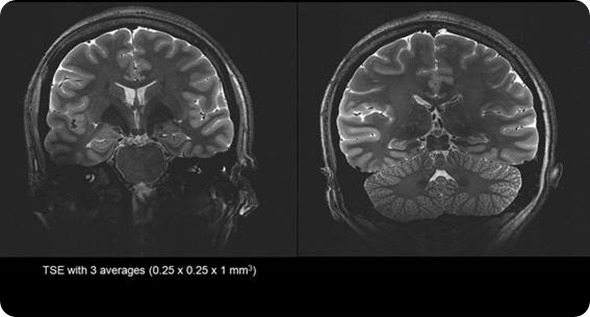

Stronger magnet fields increase the signal-to-noise ratio of the MRI signal. This increase in signal to noise can then be used to increase the spatial or temporal resolution of the image. Simply put, the higher the magnetic field strength, the more detail we can see inside the body.

Most MRI scanners operate between 1.5 Tesla and 3 Tesla.  Due to benefits of the increased resolution at higher filed strengths SMT have developed a ground breaking 7 Tesla system, the MAGNETOM Terra. This new system has been designed to meet the demands of both researchers and clinicians.

Due to the extra signal to noise available at 7 Tesla we are able to generate exquisite image quality to show vascularity of the brain without the need for an injection of contrast media often required at lower field strengths.

This allows researchers to identify lesions and bleeds more easily, and the specific areas of the body affected - potentially enabling unprecedented insights into hard-to-diagnose conditions.